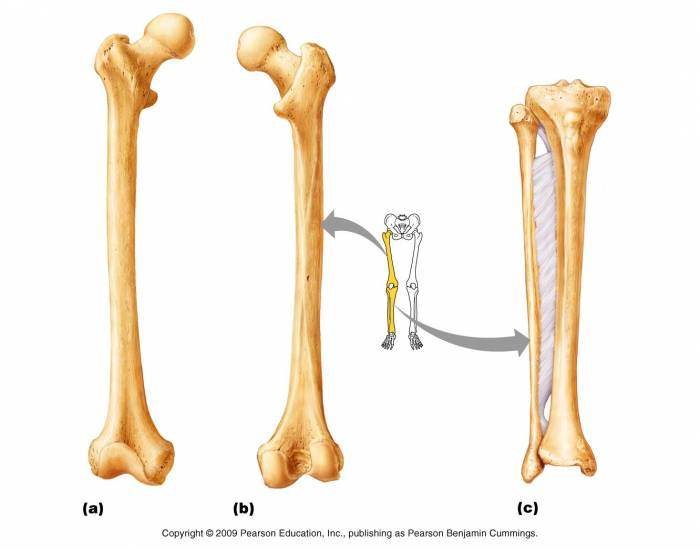

Анатомия фибулы: Подробные фотографии и схемы